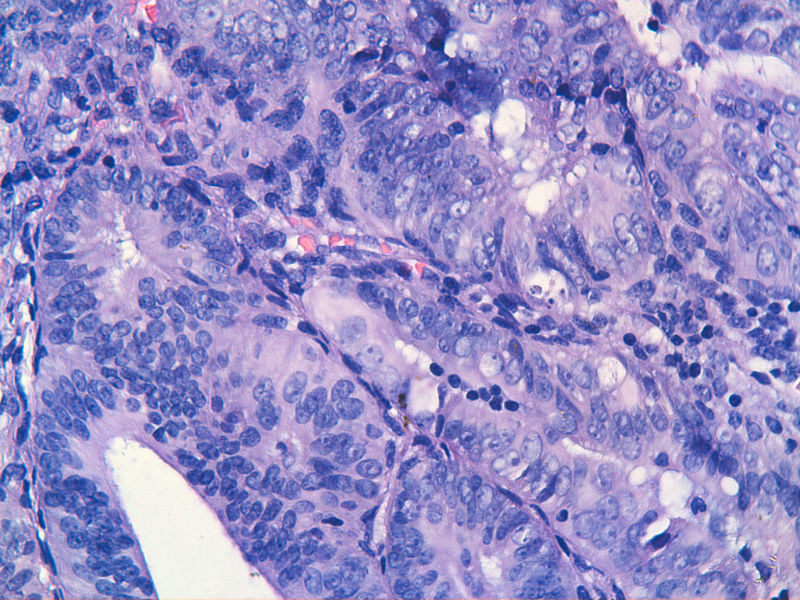

子宫内膜EIN?

子宫内膜EIN?图1

名称:图1

描述:image_2000y01m01d_08h08m34s

图13是做为正常对照的,图7、8、9、12显示的核大小不一,空泡状,形状不规则。女,48岁,宫血半年